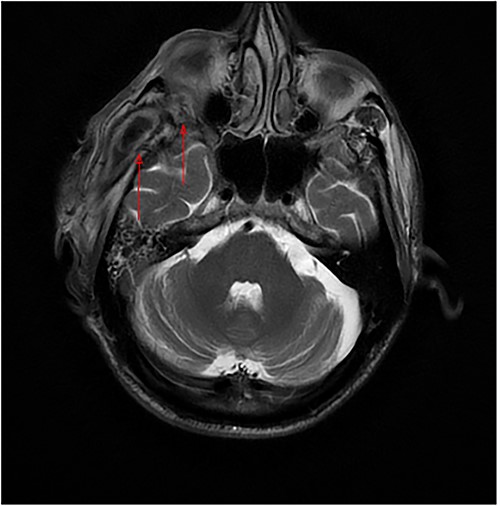

The patient’s head and neck were imaged using magnetic resonance imaging (MRI) and computed tomography scan, which revealed the presence of abscess collections in the submasseteric space, pterygomandibular space, deep temporal space and infratemporal abscess spreading to the orbital cavity through a bony defect in the lateral orbital wall, all of which were not addressed during the first procedure (Figs 2 and 3).

(a) Axial MRI of the head: a dumbbell-shaped lesion (red arrows) representing an infratemporal abscess invading the orbital cavity through the bony erosion of the lateral orbital wall. (b) Abscess localization in the deep temporal space (red arrows). (c, d) Coronal MRI of the head and neck shows an orbital abscess (red arrows) and endopthalmitis (red arrows).

Axial MRI of the head, a dumbbell-shaped lesion (red arrows) representing an infratemporal abscess invading the orbital cavity through the bony erosion of the lateral orbital wall.

Most cases of odontogenic orbital complications arise from upper jaw tooth infections [4]. What is unique about our case is the unusual route by which the infection spread into the orbit. In our case, the hypothesized path of spread started from the lower third molar infection to both the submasseteric and pterygomandibular spaces and then passed into the infratemporal fossa, where a focus of abscess was loculated, making its way into the orbit through a bony defect in the lateral orbital wall, forming an interesting dumbbell-shape appearance on MRI (Fig. 2a).